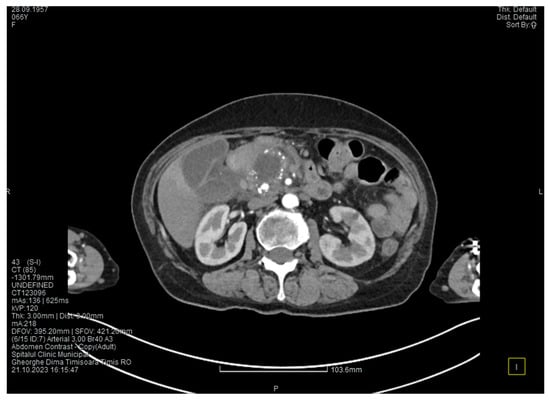

Contrast-enhanced computed tomography highlighted signs of chronic pancreatitis with multiple calcifications throughout the pancreatic parenchyma, calcareous conglomerates in the cephalic area (Figure 5), dilatation of the Wirsung duct measuring approximately 15 mm, a cephalo-uncinate pseudocyst measuring 30/31/32 mm (Figure 6), and densification of the pericephalic pancreatic fat; all the changes were more pronounced compared to the previous examinations. Other findings included acute cholecystitis with thickening of the gallbladder wall and iodophilia of the mucosa, small dilatations of the intrahepatic bile ducts, fluid accumulation in the hepatic hilum and in the periduodenal area, inflammatory wall thickening in the gastric antro-pyloric region and in the duodenum (I, II), and inflammatory lymph nodes in the peripancreatic area and in the hepatic hilum measuring up to 11 mm.

Figure 5. CT scan at the fourth episode of acute pancreatitis shows calcifications in the pancreatic head, thickening of the duodenal wall, and partial occlusion of the duodenum.

Figure 6. CT scan at the fourth episode of acute pancreatitis shows a slightly increased cyst and calcifications in the pancreatic head.